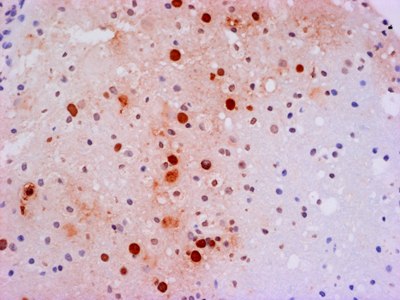

Before AIDS was even proven to be caused by a viral infection, it was clearly associated with severe neurologic disease. Beyond the devastating opportunistic infections related to severe immunosuppression, late-stage AIDS patients also exhibited a unique dementia. In retrospect, the histopathology of AIDS dementia was exactly what should have been expected for a macrophage tropic virus in a patient with severe immunosuppression, minimal to no lymphocyte infiltration in the context of abundant virus [25] (Figure 5). Indeed, the concentration of virus in the CNS exceeded that in lymphoid organs [26]. The big mystery that has yet to be solved is, How did infection of microglia in the absence of neuroglial infection lead to a clinical dementia [27]? It has been hypothesized that infected microglia either produced a neurotoxin (e.g., quinolinic acid [28]) or were unable to carry out critical physiological functions that non-infected microglia normally perform (e.g., synaptic stripping). Hypotheses range from remote or local responses to immunologic stimulation to hypothesized abortive infection of astrocytes. Before intensive investigation could elucidate the pathogenesis of AIDS dementia, highly effective anti-retroviral therapy eradicated HIV encephalitis. While HIV infected individuals still experience neurologic symptoms of unknown etiology, AIDS dementia, like syphilis dementia, disappeared.

Figure 5A. Low power H&E-stained section of cortical tissue from a patient with HIV encephalitis.

Figure 5B. Higher power H&E-stained section showing a multinucleated giant cell.